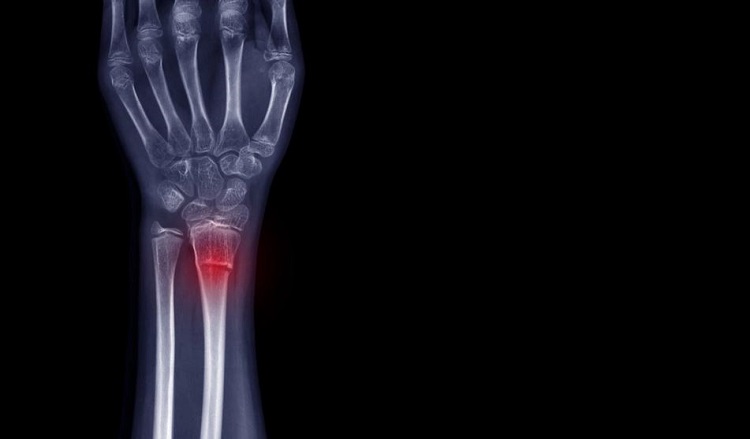

As a fracture heals, it progresses through various stages. These include clotted blood forming at the fracture, which becomes replaced by a callus of fibrous tissues and cartilage, followed by formation of a hard bony callus. The bone is then remodeled, as regular bone replaces the hard callus and the bone returns to its usual shape.

The team was able to observe the CD73-positive MSCs moving towards the site of the fracture and forming new cartilage and bone cells to heal the fracture. The CD73-positive sECs were also involved in the healing of the fracture, as they contributed to the process of 'neovascularisation', the formation of new blood vessels to support the healed bone.